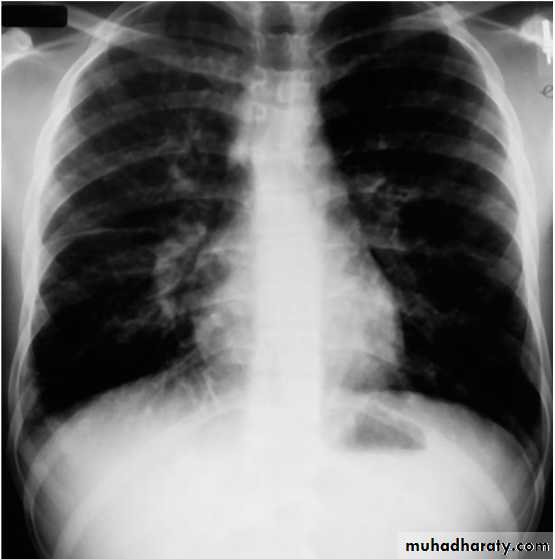

Mycoplasma pneumoniae infection (atypical pneumonia)

CXR:

Frontal & lateral:Bacterial pneumonia characteristically shows lobar consolidation, or a round pneumonia, with pleural effusion in 10% to 30% of cases.

Viral pneumonia characteristically shows diffuse, streaky infiltrates of bronchopneumonia.

Atypical pneumonia, such as with M. pneumoniae and C. pneumoniae, shows increased interstitial markings or bronchopneumonia.